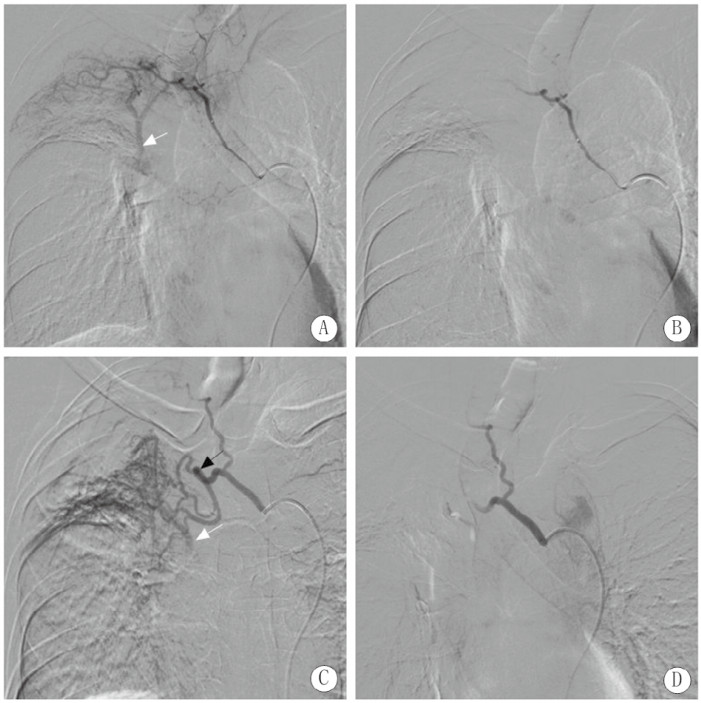

入院后每日咯血约500 mL,患者家属要求行介入栓塞止血,术中患者不间断咯血,数字减影血管造影(digital substraction antiography, DSA)示右第四肋间动脉增粗,远端可见肺静脉分支显影,右支气管动脉主干增粗与右第3肋间动脉共干,支气管动脉远端分支增多杂乱,肺组织富血管化,可见肺静脉分支显影。使用自制明胶海绵颗粒(直径约1 mm)进行栓塞止血,患者家属要求不用钢圈栓塞,栓塞后复查造影仅肋间动脉及支气管动脉主干保留,异常血管及静脉瘘消失(图 2)。栓塞后患者出血停止,术后4 d患者在排便和咳嗽后再次出现大量咯血,1 h总量超过200 mL,停用垂体后叶素半小时后再次进行介入栓塞止血治疗。术中DSA右支气管动脉主干再通,远端杂乱血管减少,支气管动脉-肺静脉瘘未显示,共干的第3肋间动脉出现假性动脉瘤(图 3黑箭头)和肋间动脉-肺静脉瘘(图 3白箭头),用泰尔茂2.7 F微导管超选后使用直径1 mm明胶海绵颗粒、COOK 2/3、2/4和2/5 mm微钢圈各一个进行栓塞后,复查造影示仅主干保留,术中还发现一支左右共干支气管动脉但与咯血无关(图 3)。术中造影还发现右第4肋间动脉再通,并通过侧支与第3肋间动脉吻合,可见假性动脉瘤显影(图 4黑箭头),肺静脉瘘(图 4白箭头)仍然存在,使用1 mm明胶海绵颗粒和COOK 2/3 mm微钢圈进行栓塞后只保留了主干;术中发现上次介入治疗时漏诊的一支血管-右第5肋间动脉,其主干增粗,远端异常血管增多,并可见肺静脉瘘形成(图 4白箭头),使用1 mm明胶海绵颗粒和COOK 2/4 mm微钢圈进行栓塞后,复查造影仅主干显影(图 4)。术后未出现并发症,术后3 d每日咳出暗红血约20 mL,之后未再出现咯血。随访3个月未见复发出血。

| 注:A为右第四肋间动脉增粗,远端可见肺静脉分支显影(白箭头),为肋间动脉-肺静脉瘘形成;B为栓塞后仅右第四肋间动脉主干显影;C为右支气管动脉主干增粗与右第三肋间动脉共干,支气管动脉远端分支增多杂乱,肺组织富血管化,并可见肺静脉分支显影(白箭头),为支气管动脉-肺静脉瘘形成;D为栓塞后复查造影肋间动脉及支气管动脉主干保留,异常血管及静脉瘘消失。 图 2 第1次介入治疗DSA图 |